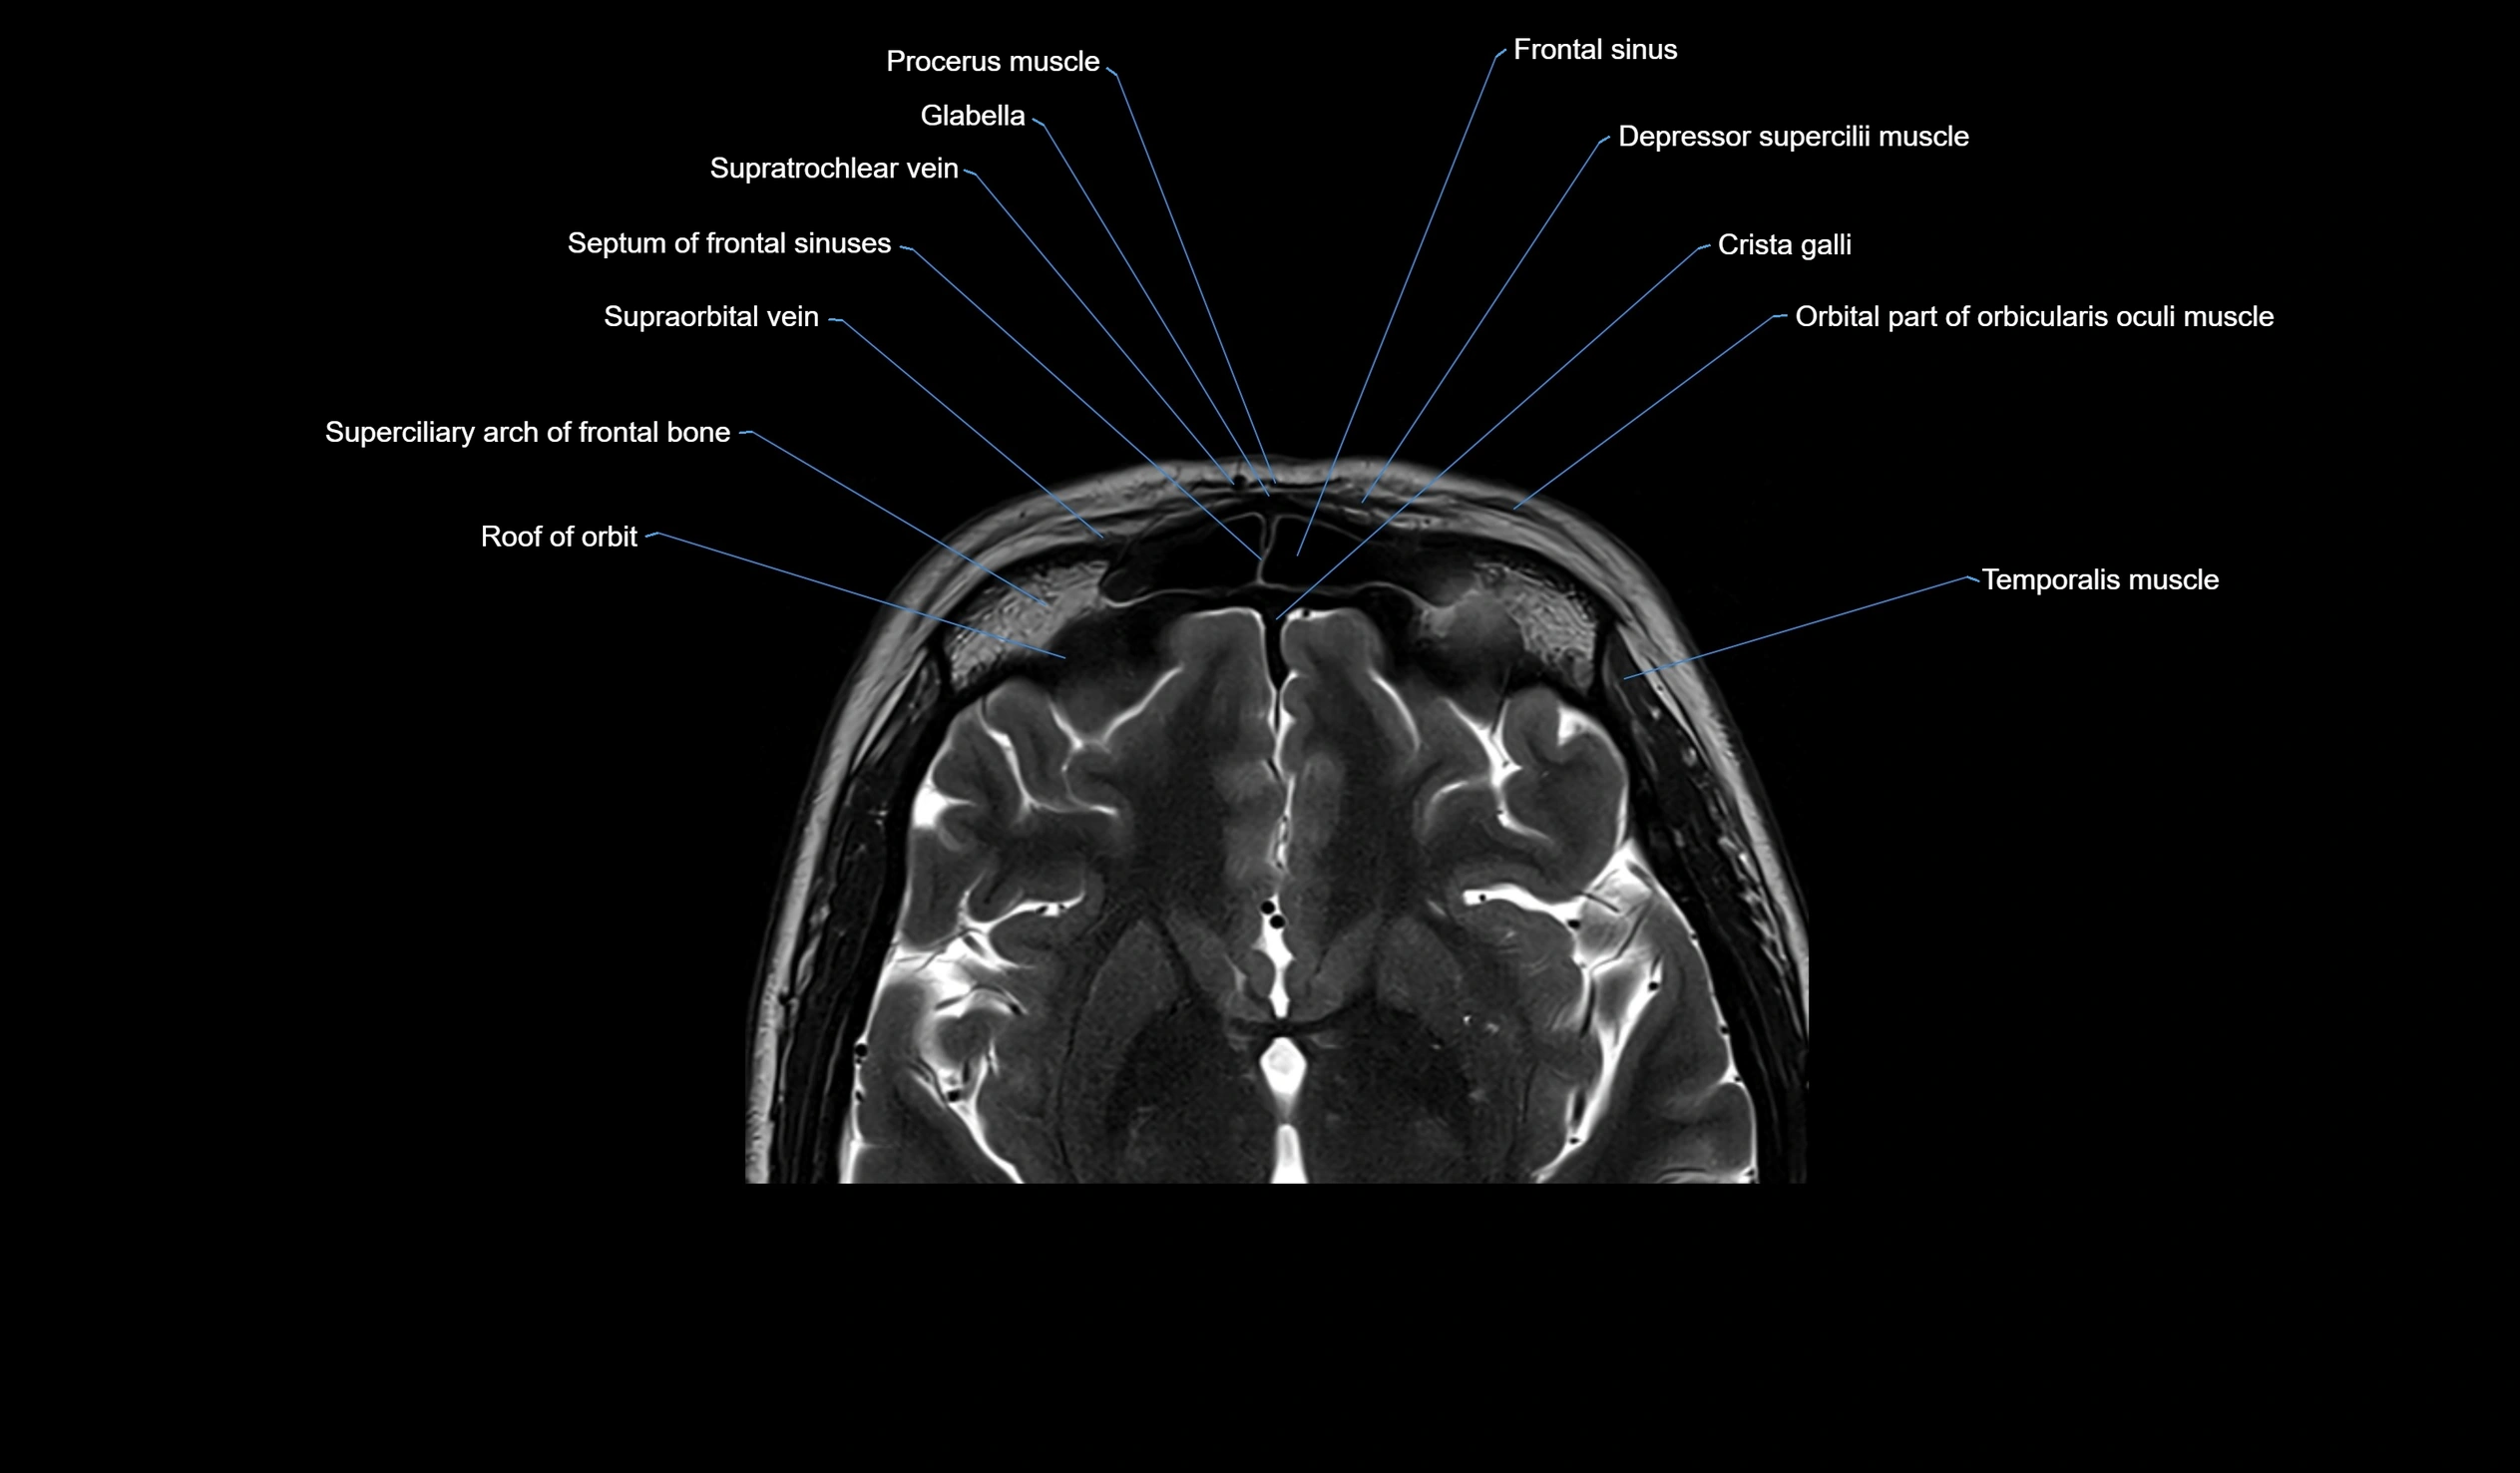

MRI images